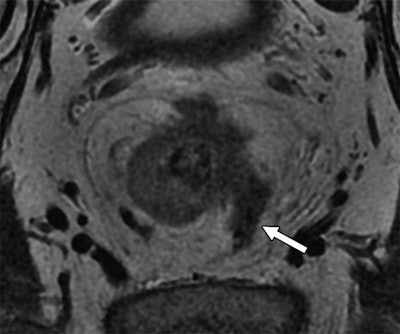

By using MRI to gauge extramural venous invasion and circumferential resection margin, the researchers found prognostic indicators that can predict which patients have a higher risk for recurrence of rectal cancer.

Extramural venous invasion status is a key component in the evaluation of a tumor surrounded by muscle or containing red blood cells. Circumferential resection margin is used to determine the risk of local recurrence in an excised tumor.

Circumferential resection margin on MRI was deemed to be a significant indicator of overall survival, disease-free survival, and local recurrence. In fact, rectal cancer patients were five times more likely to survive over a median follow-up time of 42 months based on the hazard ratio. Extramural venous invasion was significantly influential regarding disease-free survival but not so with overall survival and local recurrence of the disease.